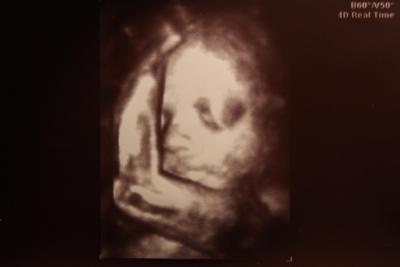

Hallo, ich war heute zum 3. großen US bei meinem FA. Vermutlich das letzte Mal, dass ich das Kleine im Bauch gesehen habe, geh ab jetzt nur noch zur Hebamme. Soweit ist aber alles super, Kind wiegt etwa 1.250 g. CTG habe ich abgelehnt, braucht ma ja nicht unbedingt. Outing haben wir nach wie vor keines, aber wir wollen ja auch ein Ü-Ei! Viele Liebe Grüße (meine ganzen Beschwerden erspare ich euch, dass wird sonst ein endlos langer Text... )

ooch wie niedlich. hat es geschlafen??? schön, dass alles in ordnung ist!

Danke euch, das Kind hat während dem US wirklich geschlafen, dabei ist es sonst immer wach! (fühlt sich zuminderst so an, vorallem wenn ich schlafen will) @sonja: Ich bin in dieser Schwangerschaft bei vielen Dingen anders eingestellt und halte so manches für Blödsinn und unnötige Panikmache, ist aber meine persönliche Meihnung... LG